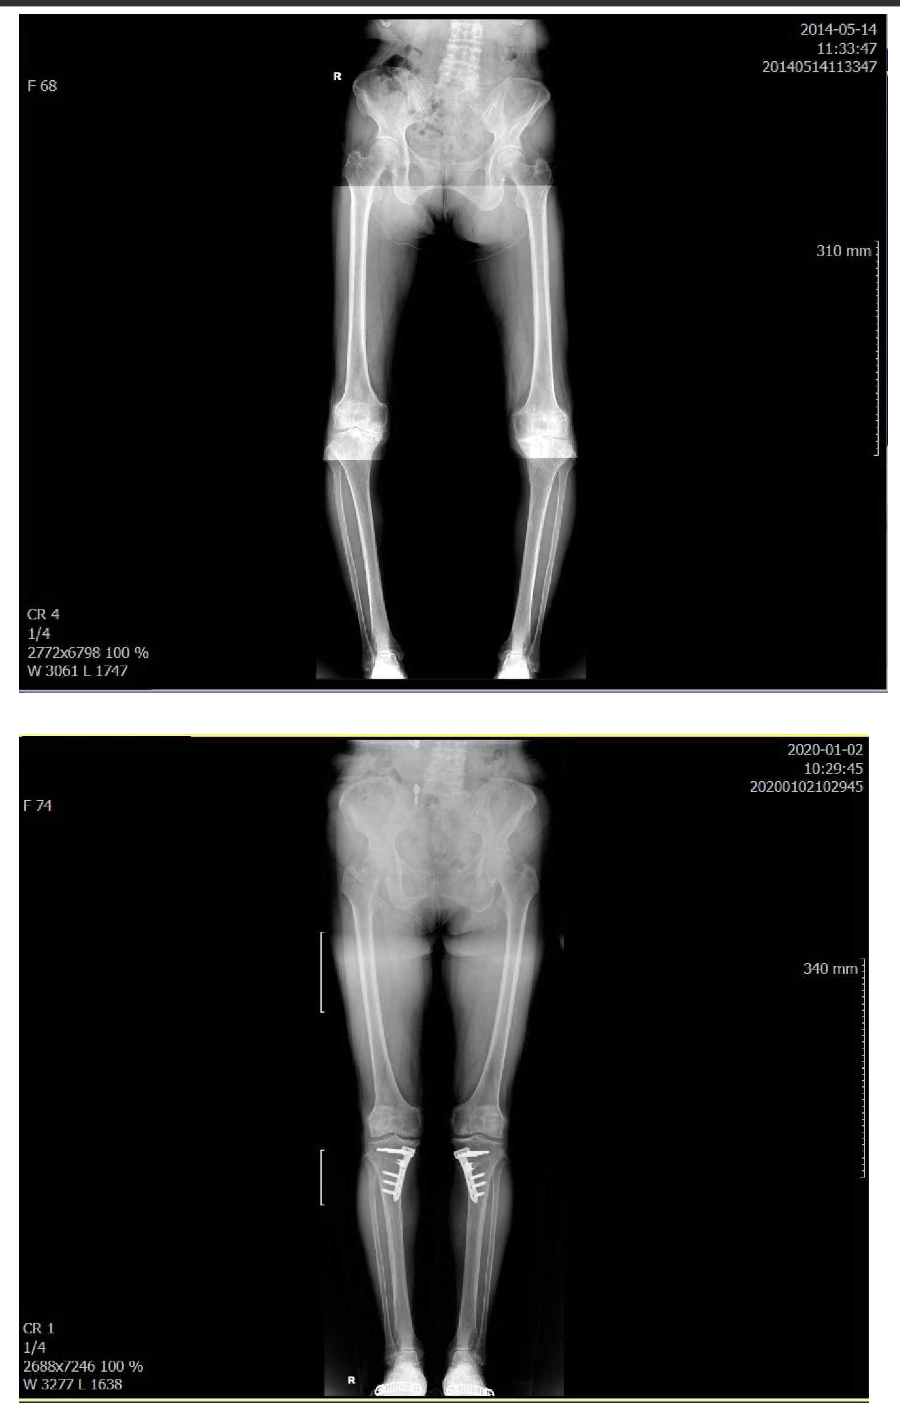

CARTISTEM (umbilical cord blood-derived stem cell) + Osteotomy (HTO) + Arthroscopy Course

This program focuses primarily on CARTISTEM (umbilical cord blood-derived stem cell) implantation for cartilage regeneration, osteotomy (HTO), and arthroscopic surgery, delivered through structured lectures, live OR observation, and post-surgery Q&A conference discussions.

The CARTISTEM® Stem Cell Cartilage Restoration Course is an advanced physician training program focused on umbilical cord blood–derived stem cell–based cartilage regeneration for knee joint preservation.

This course provides structured exposure to the clinical principles, surgical techniques, and treatment planning behind CARTISTEM®-based autologous cartilage restoration.

Participants observe and engage in real-world procedures used to repair complex cartilage defects that cannot be adequately treated with conventional methods.

Gangnam JS Hospital is a national leader in cartilage regeneration and joint preservation in Korea. This physician-focused training program delivers hands-on education in stem cell–based cartilage restoration, high-level osteotomy, and advanced arthroscopic surgery, based on protocols that define current orthopedic standards in Korea.

High-Level Osteotomy (HTO / DFO)

- Joint-preserving realignment surgery

- 3D simulation–based planning and precise biomechanical correction

- Structured rehabilitation to extend native joint lifespan